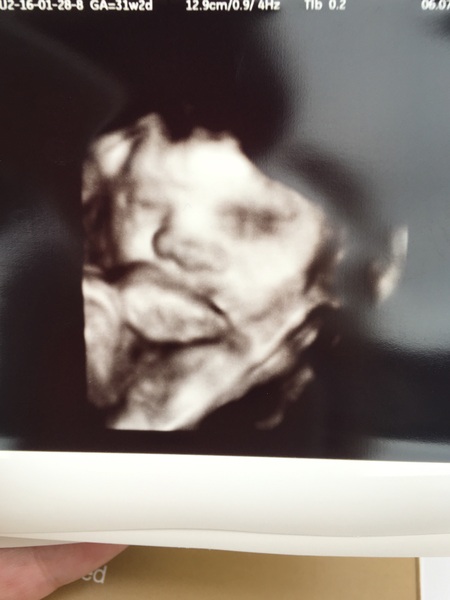

AudreyBradshaw · 07/07/2016 19:44

Scan was amazing thanks guys! And there's definitely a baby in there! Staying vanilla but was such a lovely experience and such a difference between the 12 weeks scan and today. Brain, kidneys, heart all present correct and wonderful!

IndiX · 07/07/2016 19:53

Yay great news Audrey! Cute scan pic tooSmile